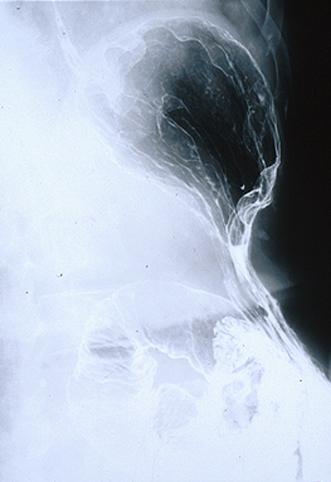

Criteria of Hist.ClassificationMalignant Lymphoma/MLP type

LocationEsophagus/More than one of the above

Technique, MethodX-ray

Size1 - 9